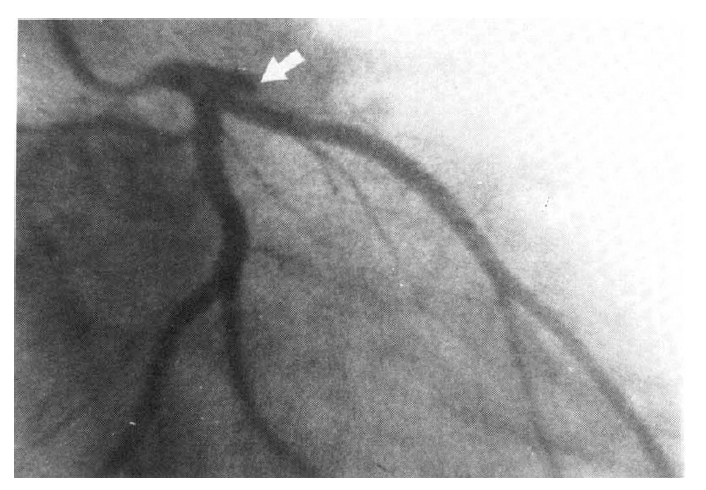

Left coronary arteriography in the right anterior oblique projection. A complete out-off of the left anterior descending coronary artery at the proximal segment is seen (arrow). No other lesion is observed.

A 29-year-old male with no previous history of heart disease was admitted to the Chest Surgery Department via the emergency room because of dyspnea and severe chest pain shortly after experiencing strainght anterior wall chest trauma by an umbrella tip. The patient had no earlier history of admission, operation, cardiac or respiratory diseases. He did not smoke or consume alcohol. There was no family history of cardiac or respiratory diseases. He was a stockbroker and was stabbd with the acute tip of an umbrella by an angry customer who had lost all of his fortune. Thirty minutes after abrupt chest pain and dyspnea, he was brought to the hospital. Physical examination on arrival revealed blood pressure of 150/100 mmHg, a regular pulse rate of 68 beats per minute, and respiration at the rate of 20 per minute. On examination, there was no visible wound on the chest wall. Carotid pulsation was normal. On auscultation there were no wheezes or rales in both lung fields. Examination of the heart revealed a regular rhythm without murmurs, clicks or pericardial rubs. The electrocardiogram (ECG) showed abnormal Q waves with an ST elevation on leads V2–V4 (Fig. 1). The chest X-ray film revealed cardiomegaly with cardiothoracic ratio 0.55 and no bony fracture. Serum LDH was 1257 IU/l, SGOT 646 IU/l, and CPK 365 IU/l. White blood cell count was 13,600/ml. Urinalysis and routine blood chemistry, including fasting blood glucose and cholesterol, were all within normal limits. An echocardiogram revealed hypokinesia of the anteroseptal wall and dyskinesia of the apical wall. A left ventriculogram and coronary arteriograms were performed 3 weeks after admission. Coronary arteriography revealed a total occlusion of the proximal segment of the left anterior descending coronary artery (Fig. 2). A ventriculogram showed an area of hypokinesia on the anterobasal segment, as well as dyskinesia on the anterolateral and apical segments (Fig. 3). The patient had an uneventful hospitalization, and 3 weeks after admission he was discharged. The patient is asymptomatic at this time.

Coronary arteriography can deliniate the site and nature of the coronary occlusion. The anatomic position of the coronary circulation pathways accounts for the fact that the left anterior descending coronary artery is the one most frequently affected in this type of chest trauma33). Coronary arteriograms and a ventriculogram of our case showed total occlusion of the left anterior descending coronary artery at the proximal segment, and area of hypokinesia on the anterobasal segment, and dyskinesia on the anterolateral and apical segment. Recanalization of an occluded artery may occur, and so a delay between the trauma and a coronary arteriography may falsely increase the number of cases with normal coronary arteres at angiography.